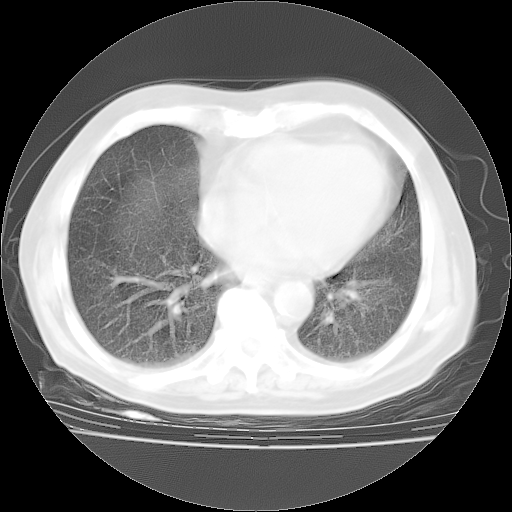

4月28日肺部CT——再次出现类似去年5月9日——透光度降低,“间质性”改变。

4月28日肺部CT——再次出现类似去年5月9日——磨玻璃样、间有“粟粒样”改变。

个人阅读4.14日肺部CT平扫:纵隔窗无异常,但肺窗示:双下肺内、后基底段有片絮状侵润影,部位以后基底段为著,以间质改变为主,呈急性肺泡炎征像,和首次住院影像学有相似之处。仅是个人读片,明日请相关专家再读片哈。其它建议同上。

1、108#的是4月14日的胸部CT(发此贴时还没看着28日的CT)。14日的胸部CT其实已经出现改变(如108#所述),个人认为28日的胸部CT除纵膈窗疑似有双侧胸膜增厚或少量胸积液(可行胸部B超明确)外,与4月14日对照病变有所加重;2、已经给予“异烟肼、利福平、乙胺丁醇”抗痨治疗?如果是,甲强龙80mg可缓慢减量;如果环磷酰胺已停用,暂不使用;3、中性粒细胞92%,明显升高,目前体温情况?注意合并细菌感染可能,使用左氧氟沙星情况下,是否联用B-内酰胺类抗菌药物?另外是查免疫全套非风湿全套。

今请临免主任会诊后认为:4月14日胸部CT已有双下肺间质性改变。患者病情复发多系激素减量过快不正规所致。目前甲强龙80mg/日,一周后酌情开始减量,不易过快。环磷酰胺若已停用,暂不使用。他同意目前抗菌药物使用,但应考虑是否加用B-内酰胺类抗菌药物(中性细胞明显增高);2、结核复发目前依据不足;3、若免疫全套各项指标正常,考虑多系特发性肺间质炎可能大。4、加强支持,并注意保护胃黏膜。

今上午去请教了临免、呼吸主任:1、介绍病史和阅读系列胸部CT一致认为:患者肺结核不考虑,仍为肺间质纤维化,目前处于急性肺泡炎阶段。2、若仍发热,可将甲强龙增至:80mg Bid静滴,同时鉴于中性增高,合并细菌感染可能,继续左氧氟沙星治疗,再联用B-内酰胺抗菌药物,如头孢哌酮--舒巴坦;3、停用抗痨药;4、目前甲强龙每日剂量160mg ,体温正常后再酌情减量;目前暂不用免疫抑制剂;4、不建议使用免疫增强剂等;5、加强支持治疗,鼓励患者进食;5、注意随访肝、肾功及血常规情况;6、因患者目前激素用量较大,加用胃黏膜保护剂,防止消化道出血可能。